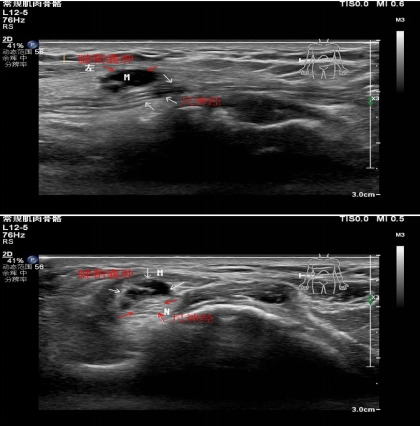

1.腕管綜合征??

2.肘管綜合征